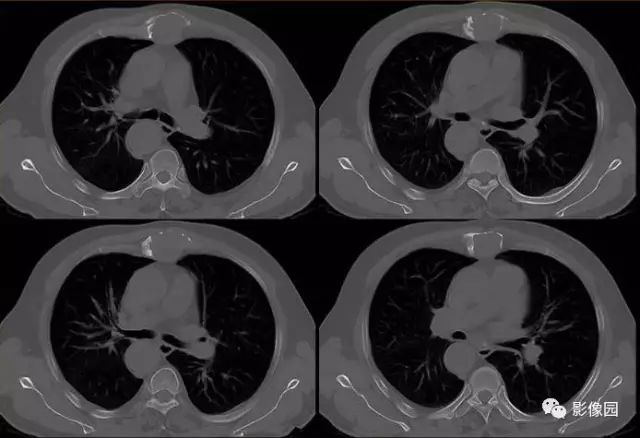

胸骨浆细胞骨髓瘤1例CT影像表现

【基本资料】男,66岁

【主诉】发现胸骨隆起1年余

【现病史】患者于1年前发现胸骨局部隆起,无红肿热痛,当时未予治疗,近来自觉隆起明显增大,伴胸前区隐痛不适。

【专科检查】胸骨上段局部隆起,压痛明显,胸部呼吸运动正常

肚肚丫头: 胸骨体局部呈膨胀性骨质吸收破坏,内呈软组织密度影,可见点状钙化,增强扫描呈轻度强化,周围软组织略肿胀。考虑:1.骨巨细胞瘤;2.浆细胞瘤;3.嗜酸性肉芽肿

【病理结果】(胸骨占位)符合浆细胞骨髓瘤

CT表现:特征性穿凿状、鼠咬状及蜂窝状骨破坏,边缘清楚,骨质疏松,病理性骨折及软组织肿块等表现,骨质硬化及骨膜反应少见。

骨破坏区完全为软组织取代,骨质膨胀,边界清楚,常突破骨皮质形成软组织肿块。增强扫描可见病灶轻中度强化,一般于静脉期达峰值。